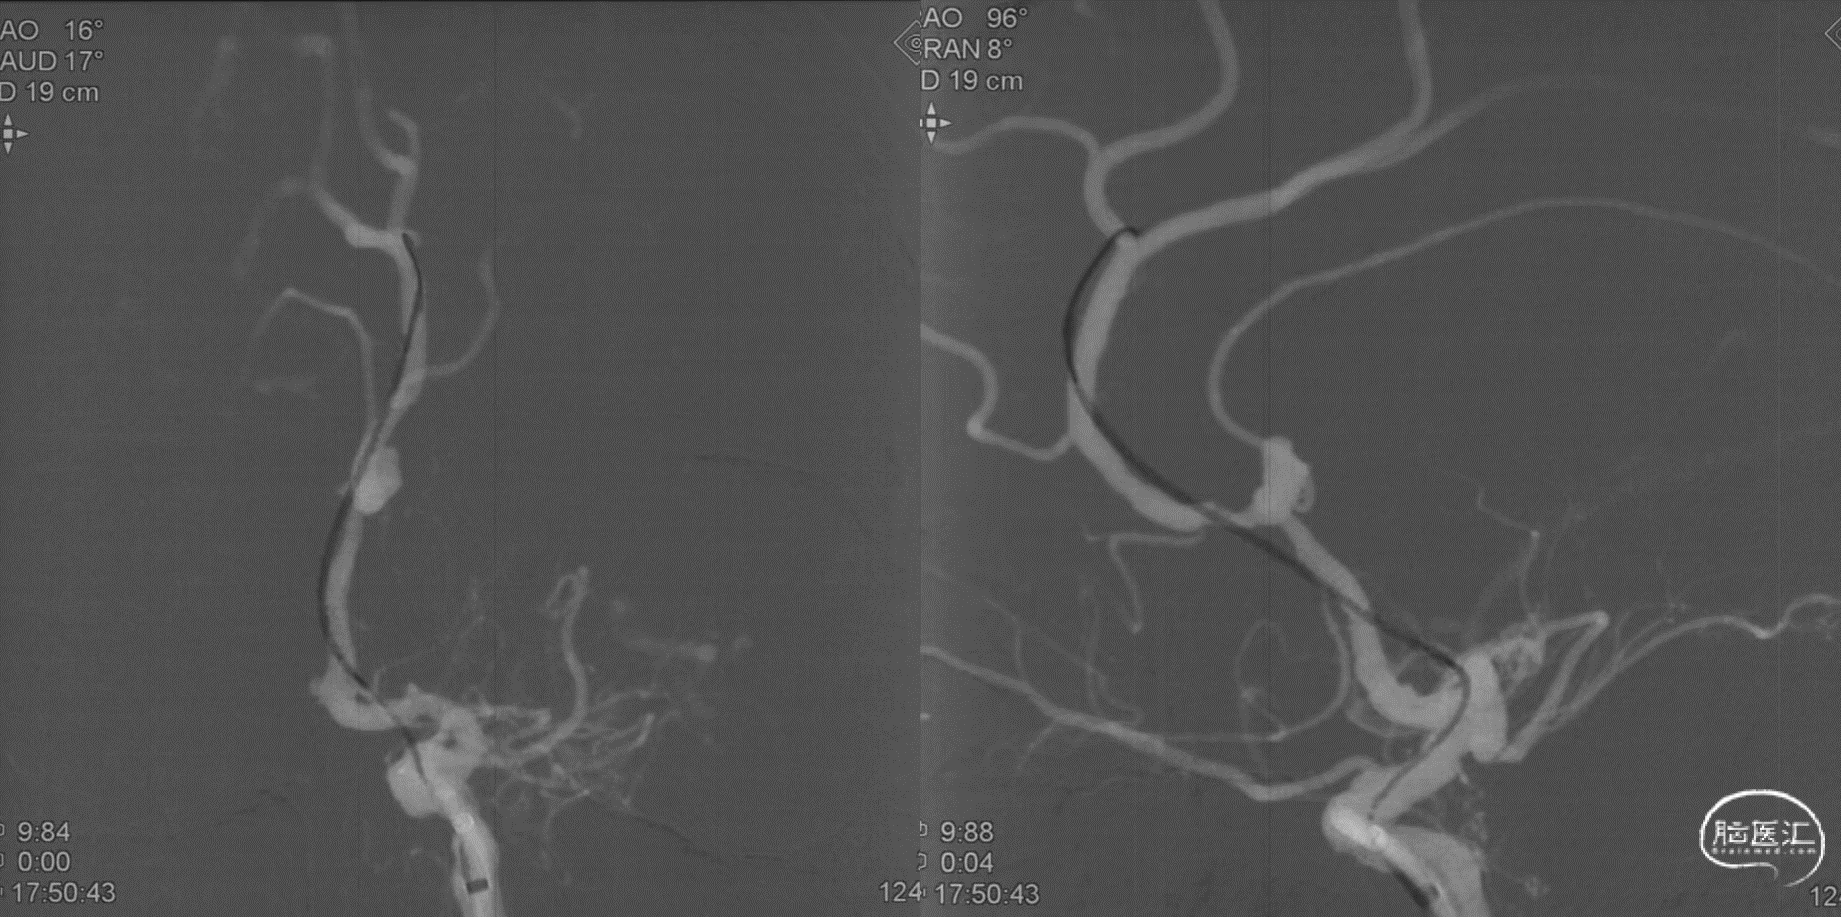

本例患者是左侧大脑前动脉A2段动脉瘤,形态不规则,合并载瘤动脉狭窄,采用血流导向装置植入治疗后获得较好的影像学结果。